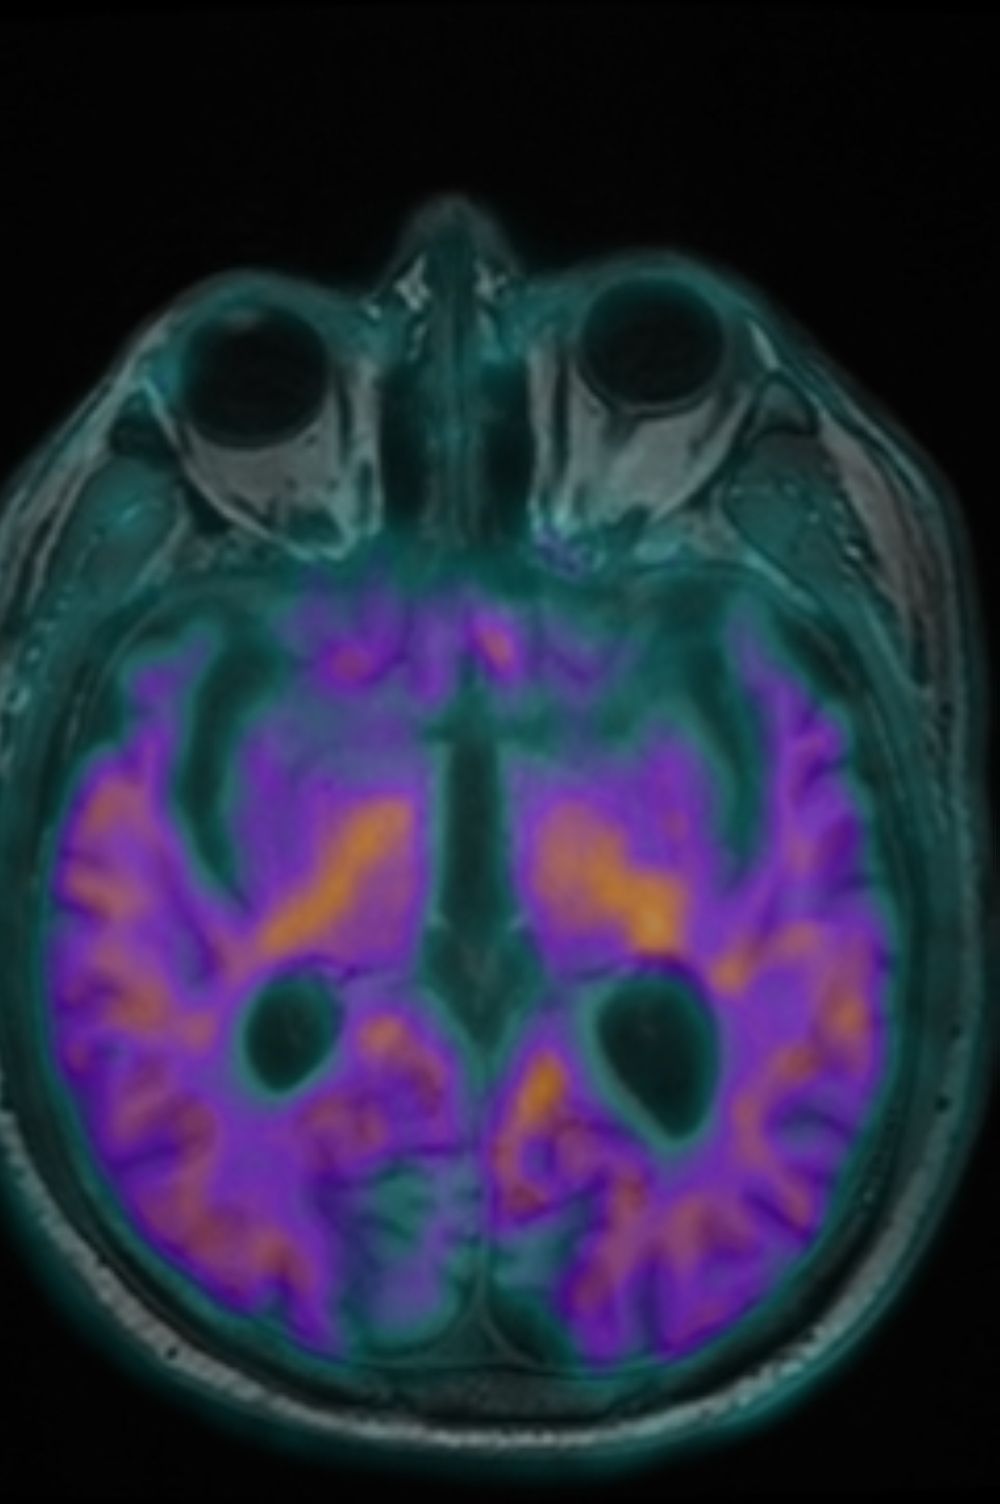

الدمام - شريف احمد - دشن مركز التصوير الجزيئي I-One، التابع لشركة وادي جدة، الذراع الاستثماري لجامعة الملك عبدالعزيز، اليوم الاثنين 15 ديسمبر 2024م، خدمة التصوير الجزيئي Amyloid PET MRI لتشخيص مرض الزهايمر، وذلك بالتعاون مع شركة Oryx Isotopes لإنتاج وتوريد مادة Amyloid (18F – FBB).

بهذا التدشين، أصبح مركز التصوير الجزيئي I-One الأول والوحيد على مستوى الشرق الأوسط الذي يقدم خدمة تشخيص مرض الزهايمر باستخدام تقنية PET/MRI، مما يعزز مكانته الرائدة في مجال التصوير الجزيئي على المستويين المحلي والإقليمي.